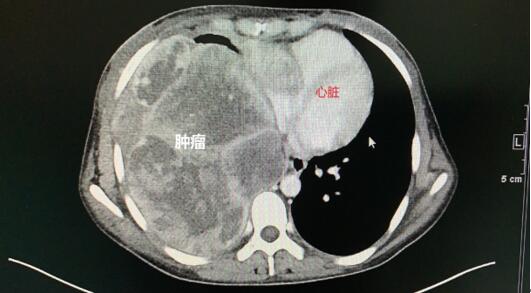

术中,医生见范小姐的肿瘤巨大,胸膜粘连严重,探查见肿物累及心包、膈肌,同时还与右下肺叶粘连紧密。术程相当困难,需要同时将侵犯的心包和膈肌部分连同肿瘤整块完整切除:心包里就是跳动的心脏和心脏大血管,若损伤心脏大血管,其后果不堪设想!肿物巨大,其本身就遮挡大部分手术视野,必须通过默契严谨的配合和充分的视野暴露,才能避免损伤视野盲区的重要器官。通过林鹏教授及杨寒医生熟练与默契的配合,最终成功将肿物连同侵犯的心包及膈肌部分完整切除取出。

然而这只是手术的第一步!林鹏教授继续评估患者情况,发现患者的右下肺因肿瘤长期压迫已丧失功能,如果保留右下肺叶,术后将产生严重的后果甚至威胁生命,遂进一步切除患者右下肺叶。最后,林鹏教授对缺损部位的心包和膈肌进行修复重建,恢复心包和膈肌结构和功能,手术终于得以圆满成功!